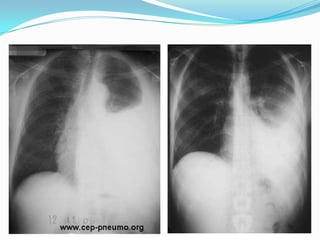

Dissection Aortique:  Dlà début subaigüe, antérieure, prolongée, irradiant dans le dos, à type de déchirement avec caractère migratoire.  S. clinique: apparition souffle diastolique Ao, asymétrie TA, abolition d’1 pouls, état de choc et trouble neurologique déficitaire.  Facteurs favo: HTA ancienne mal contrôlée, athéromateux, syndrome de Marfan.  ECG: normale éliminant IDM.  Radio pul: élargissement médiastin supérieure.  Echocardiographie confirme Dg compléter par TDM ou IRM thoracique.